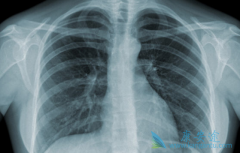

癌症免疫疗法PD-1抗体治疗KRAS突变型肺癌的效果怎么样?

KRAS突变型肺癌 是PD-1/PD-L1抑制很好的靶点。首先,KRAS突变型NSCLCs,作为典型的与吸烟有关的肺癌,通常是具有高度突变负担的癌症。第二,这些肿瘤经常显示大量的t细胞浸润。第三,相关研究表明,大约24-55%的KRAS突变型肺腺癌具有肿瘤细胞PD-L1的表 ...